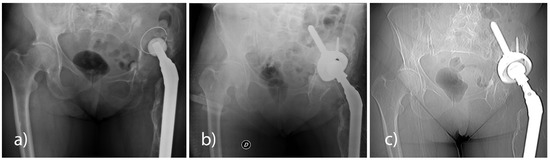

Compared to the first CT exam (5–10 weeks), the 12-month CT follow-up in all the analysed patients revealed a statistically significant reduction (p < 0.001) of the bone gap, both in the axial plane (23%) and in the coronal plane (21%). With the use of either the Sansone iliac stem cup or the press-fit cup without an iliac stem, a reduction of the bone gap was revealed in the axial plane and the coronal plane at the 12-month CT follow-up (Table 10 and Table 11, Figure 2).

Figure 2. (a) Axial and (b) coronal CT views for bone gap measurement.